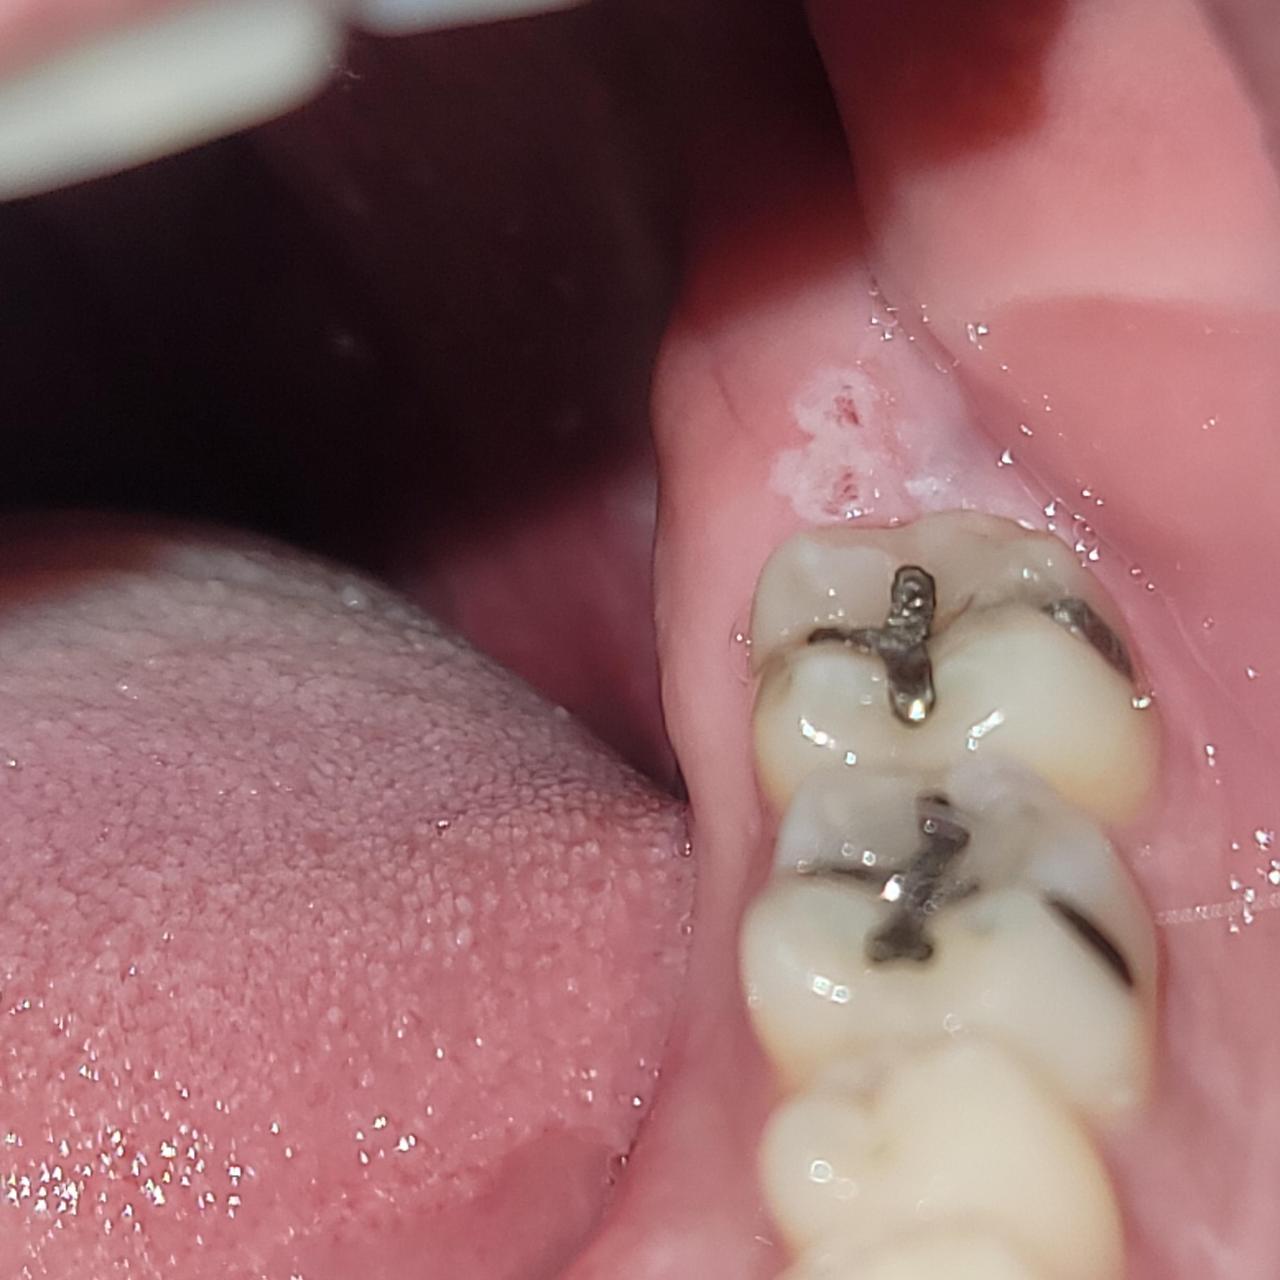

2. 잇몸 상처의 증상

잇몸 상처가 생기면 다음과 같은 증상이 나타날 수 있습니다:

- 붉은 염증 : 상처가 있는 부위가 붉고 부풀어 오릅니다.

- 출혈 : 잇몸에서 피가 나거나, 양치할 때 출혈이 발생할 수 있습니다.